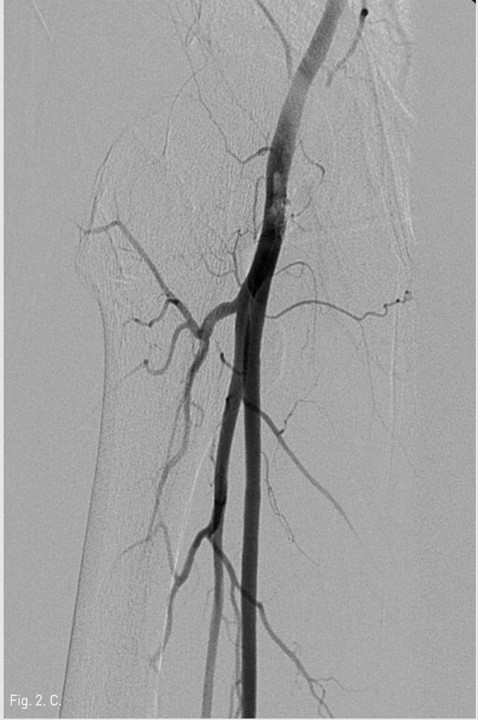

Fig. 2. C

Fig. 2C, D. Final right lower extremity angiograms show complete obliteration of pseudoaneurysm in the right common femoral artery with no embolism to the distal part of the right lower extremity arteries.